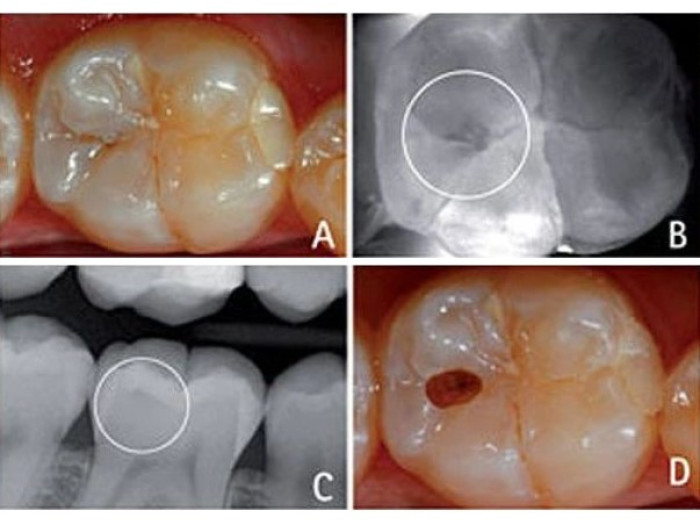

Данный случай показывает, что с помощью DIAGNOcam можно обнаружить обширные кариозные очаги. Как и в первом случае, визуальный осмотр контактной поверхности (А) не позволяет заподозрить наличие паталогического процесса.

При исследования DIAGNOcam обнаружен обширный кариозный очаг, клинически не выявленный (B). Такие повреждения можно обнаружить и при рентгеновском исследовании (C). В данном случае было принято решение об экскавации кариозной области с применением традиционных ротационных боров и последующей реставрацией композитным материалом. На изображении (D) показано, как выглядел зуб до процедуры пломбирования.